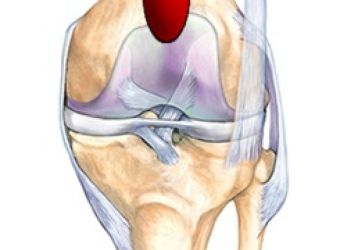

Супрапателлярный бурсит коленного сустава — симптомы и методы лечения

Cупрапателлярный бурсита коленного сустава, в чем его особенность? Способы диагностики и лечения. Медикаментозная терапия.